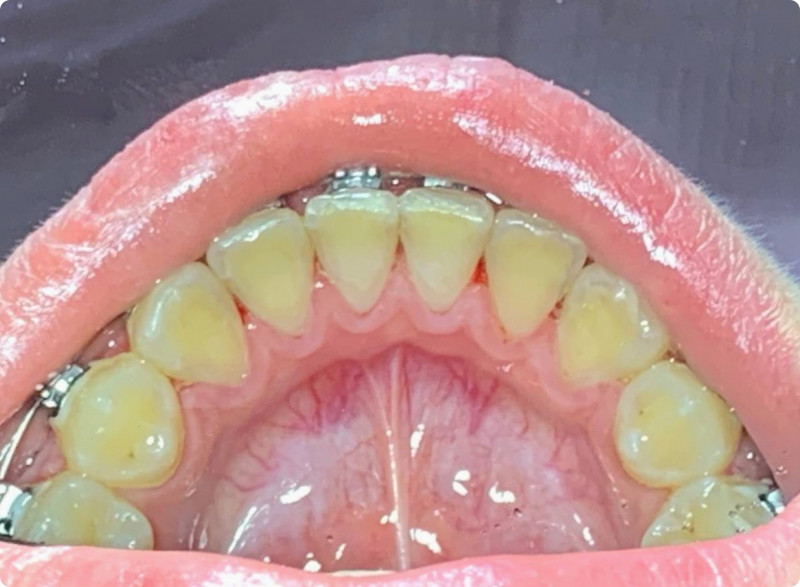

Чистка зубов Air-flow

Доктор: Трингорт Станислав Альбертович

Комплексная чистка зубов в 4 этапа: Ультразвуковая обработка, Air Flow, полировка с щеткой и пастой, капа с реминерализирующим гелем. Врач Трингорт С.А.